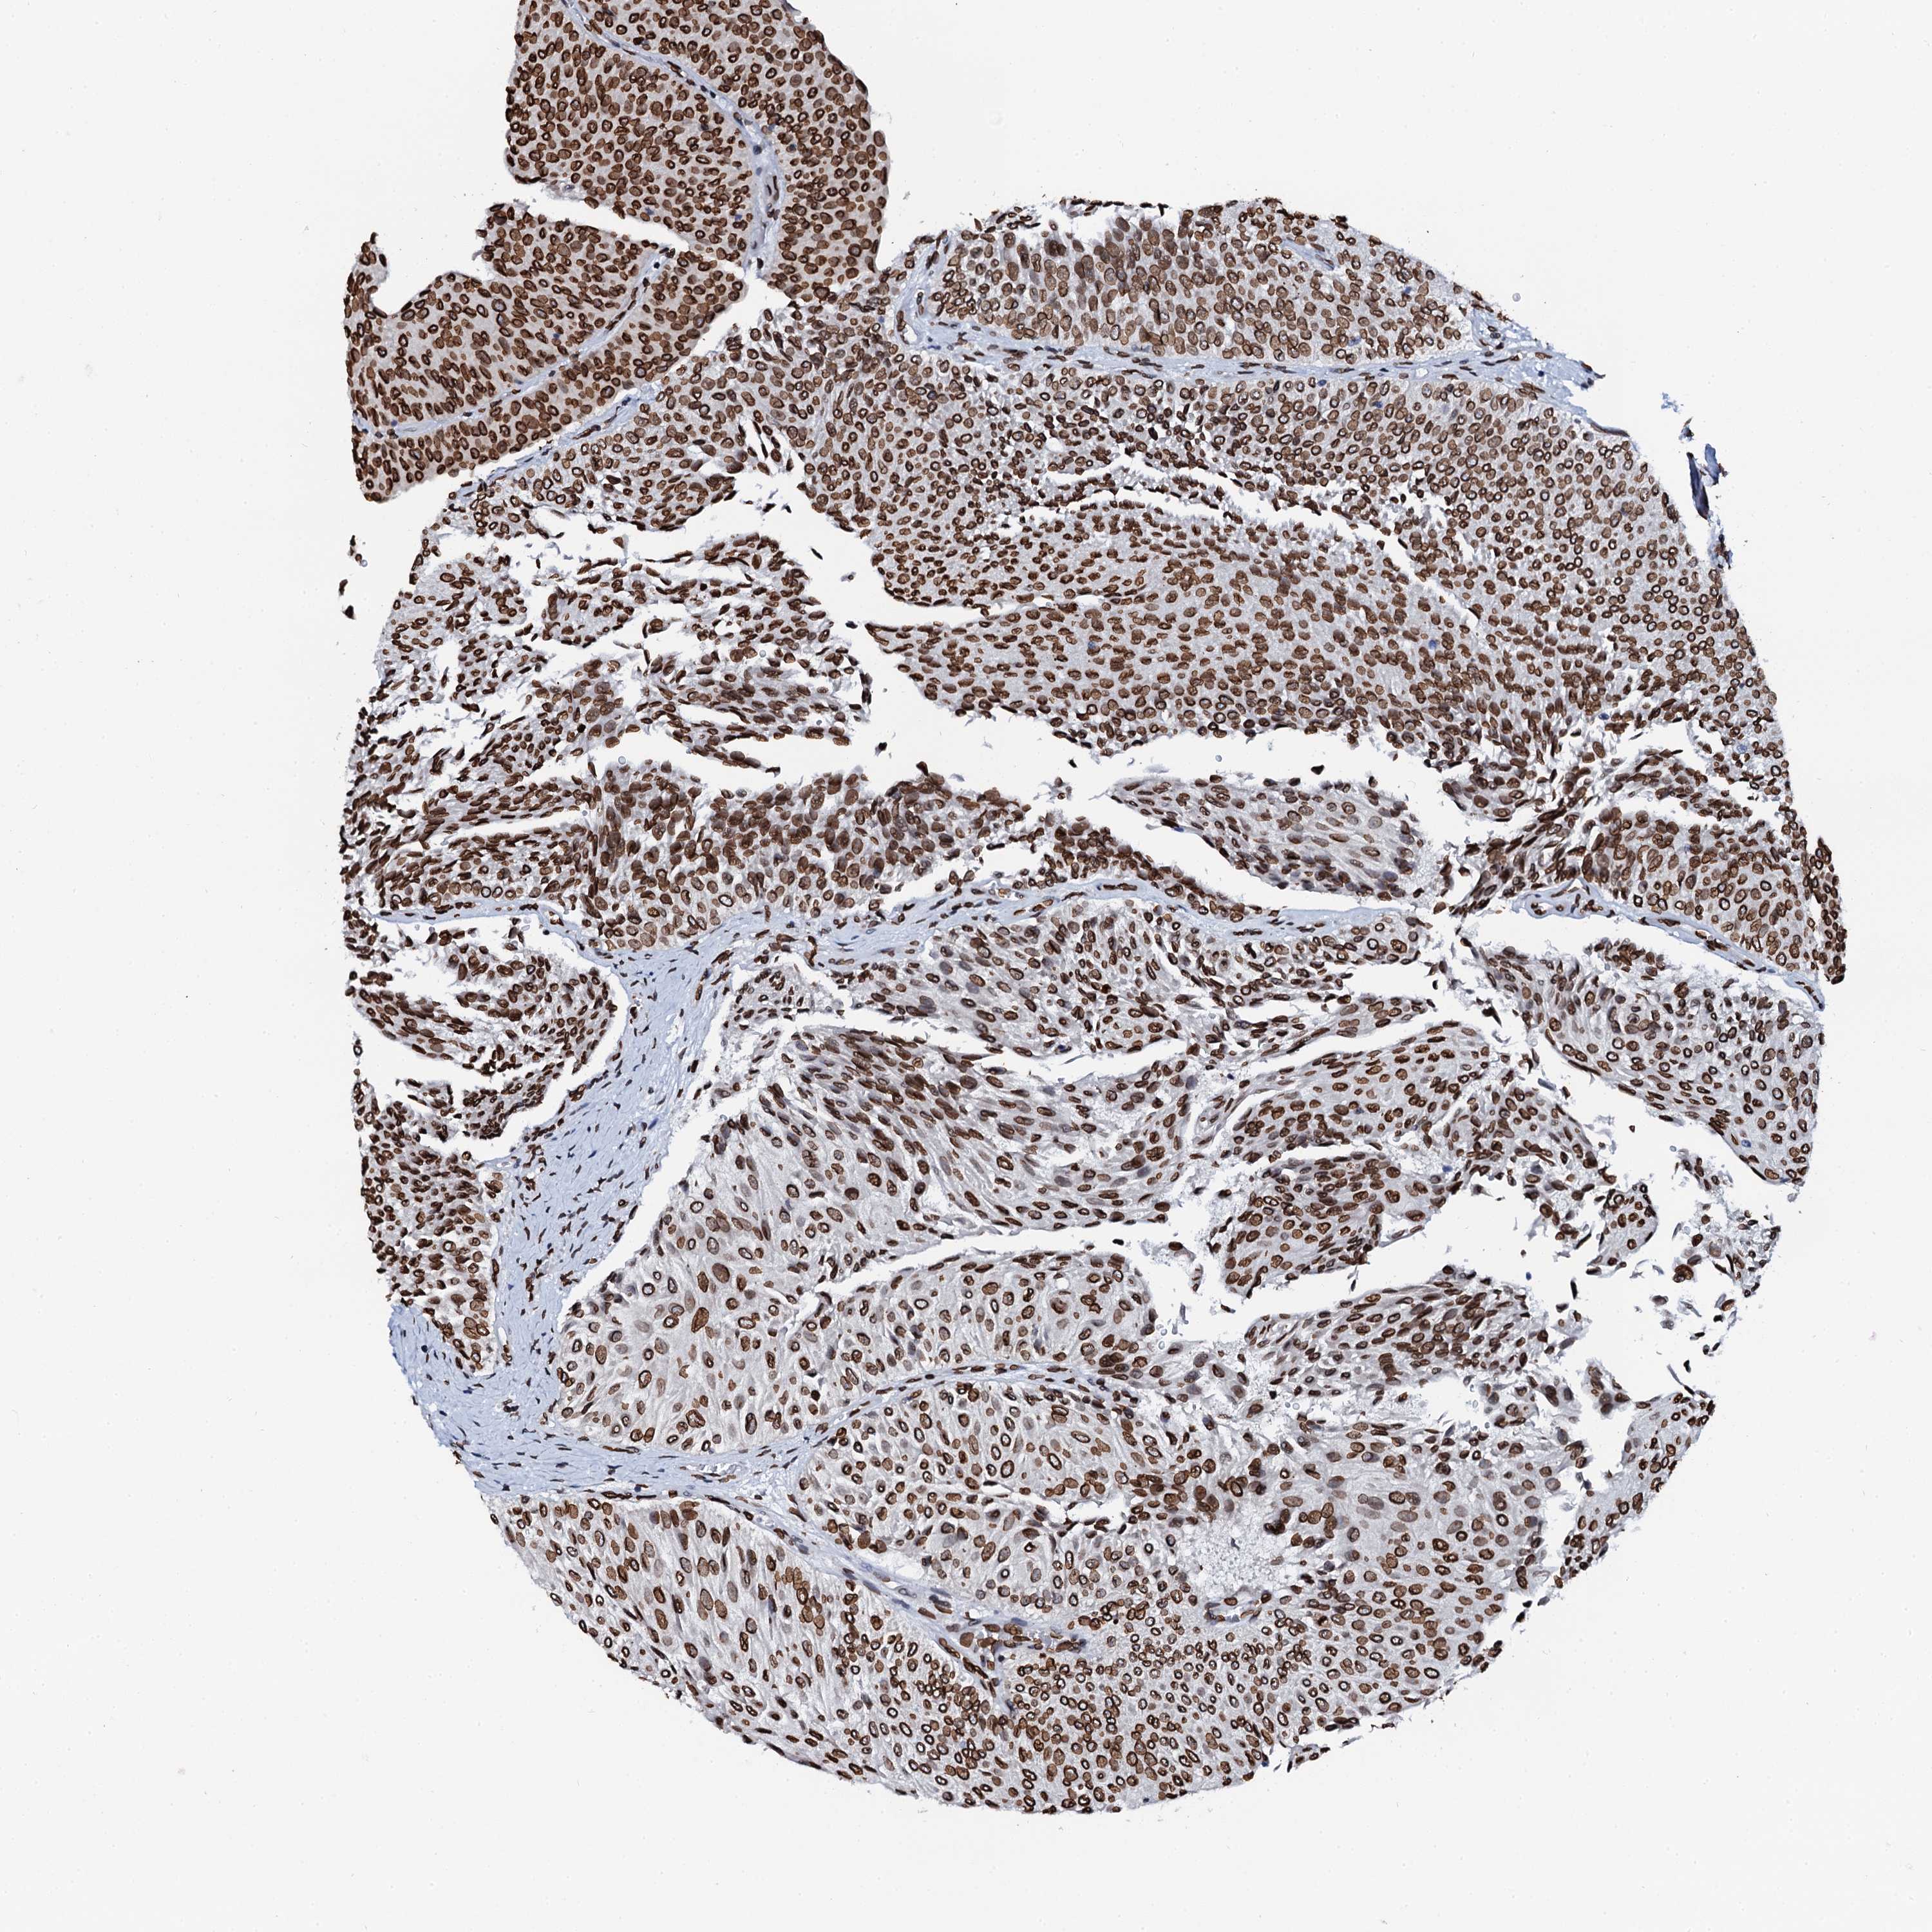

UROTHELIAL CANCER - Protein expressioni

A mouse-over function shows sample information and annotation data. Click on an image to view it in a full screen mode. Samples can be filtered based on level of antibody staining by selecting one or several of the following categories: high, medium, low and not detected. The assay and annotation is described here.

Note that samples used for immunohistochemistry by the Human Protein Atlas do not correspond to samples in the TCGA dataset.

Antibody stainingi

Antibody staining in the annotated cell types in the current human tissue is reported as not detected, low, medium, or high, based on conventional immunohistochemistry profiling in selected tissues. This score is based on the combination of the staining intensity and fraction of stained cells.

Each image is clickable and will lead to virtual microscopy that enables deeper exploration of all samples and also displays staining intensity scores, fraction scores and subcellular localization as well as patient and tissue information for each sample.

Antibody HPA040712

Antibody HPA042029

Urothelial carcinoma, Low grade

Urothelial carcinoma, High grade

Urothelial carcinoma, NOS